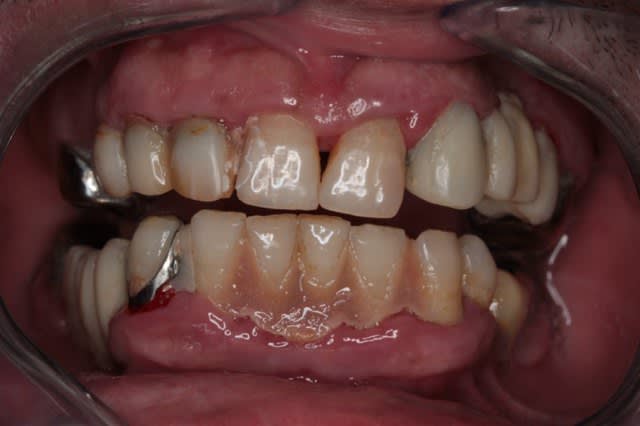

plus sérieusement mais suffisamment imparfait pour qu'on puisse trouver...

Kem inf ap neluwo - Eugenol

Kem sup2 ap bamol9 - Eugenol

pour faciliter le chmilblick : sur une arcade il y a une seule prothèse visible et sur l'autre il n'y a qu'une seule dent naturelle visible

il s'agit d'un mix de facettes et couronnes céramo-céramiques

32 et 23

bravo Henri